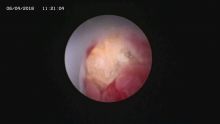

多镜联合治结石 4月6日,处于休假期间,但绥宁县人民医院泌尿外科的医护没有休息,在科主任张华生的带领下,打破常规,挑战高度,成功完成了一台复杂的结石手术。 据悉,患者姓杨,是一位60岁的男性患者,因"间断性左侧腰痛2年,再发伴尿痛2天"入院,经检查后发现患者左肾、左侧输尿管、膀胱内均有多发结石。针对这种结石,传统的手术方法至少需要开3刀,且需分期进行,使得患者痛苦大、治疗周期延长,费用也相应增高。肾结石开刀手术后劳动力会严重散失,即使采用现在流行的微创手术,常规也得分期进行,患者免不了多次手术的痛苦。为进一步减轻患者痛苦,绥宁县人民医院泌尿外科的医师们经过慎重考虑,决定打破常规,制定了多镜联合取石的手术方案。手术在4月6日顺利进行,术中联合膀胱镜、输尿管镜、经皮肾镜进行了长达70分钟的治疗,使得出血量不超过5mL且伤口仅0.5cm,一次性将患者膀胱,左侧输尿管,左肾结石全部取出。术后第五天经复查无任何结石残留,4月13日患者顺利出院。 目前,绥宁县人民医院泌尿外科在微创手术治疗各种尿路结石的技术上,己非常熟练。结石在整个邵阳地区发病率都很高,平常多喝水,每天饮水2000ml以上,调节饮食生活习惯,坚持锻炼可以有效预防结石发生,定期的健康体检也是预防结石的有效措施之一,可以早期发现结石,及时治疗。(图文 付志峰 编辑 谢雅玲) 图为:泌尿外科主任张华生、副主任付志峰进行手术时场景 图为:膀胱结石显象→手术碎石中显像→膀胱结石碎石后显像 图为:输尿管结石显像→输尿管结石碎石后显像 图为:肾结石显像→取出的肾结石标本 图为:术中建立穿刺通道 图为:术后留置的引流管 图为:术后伤口情况 |